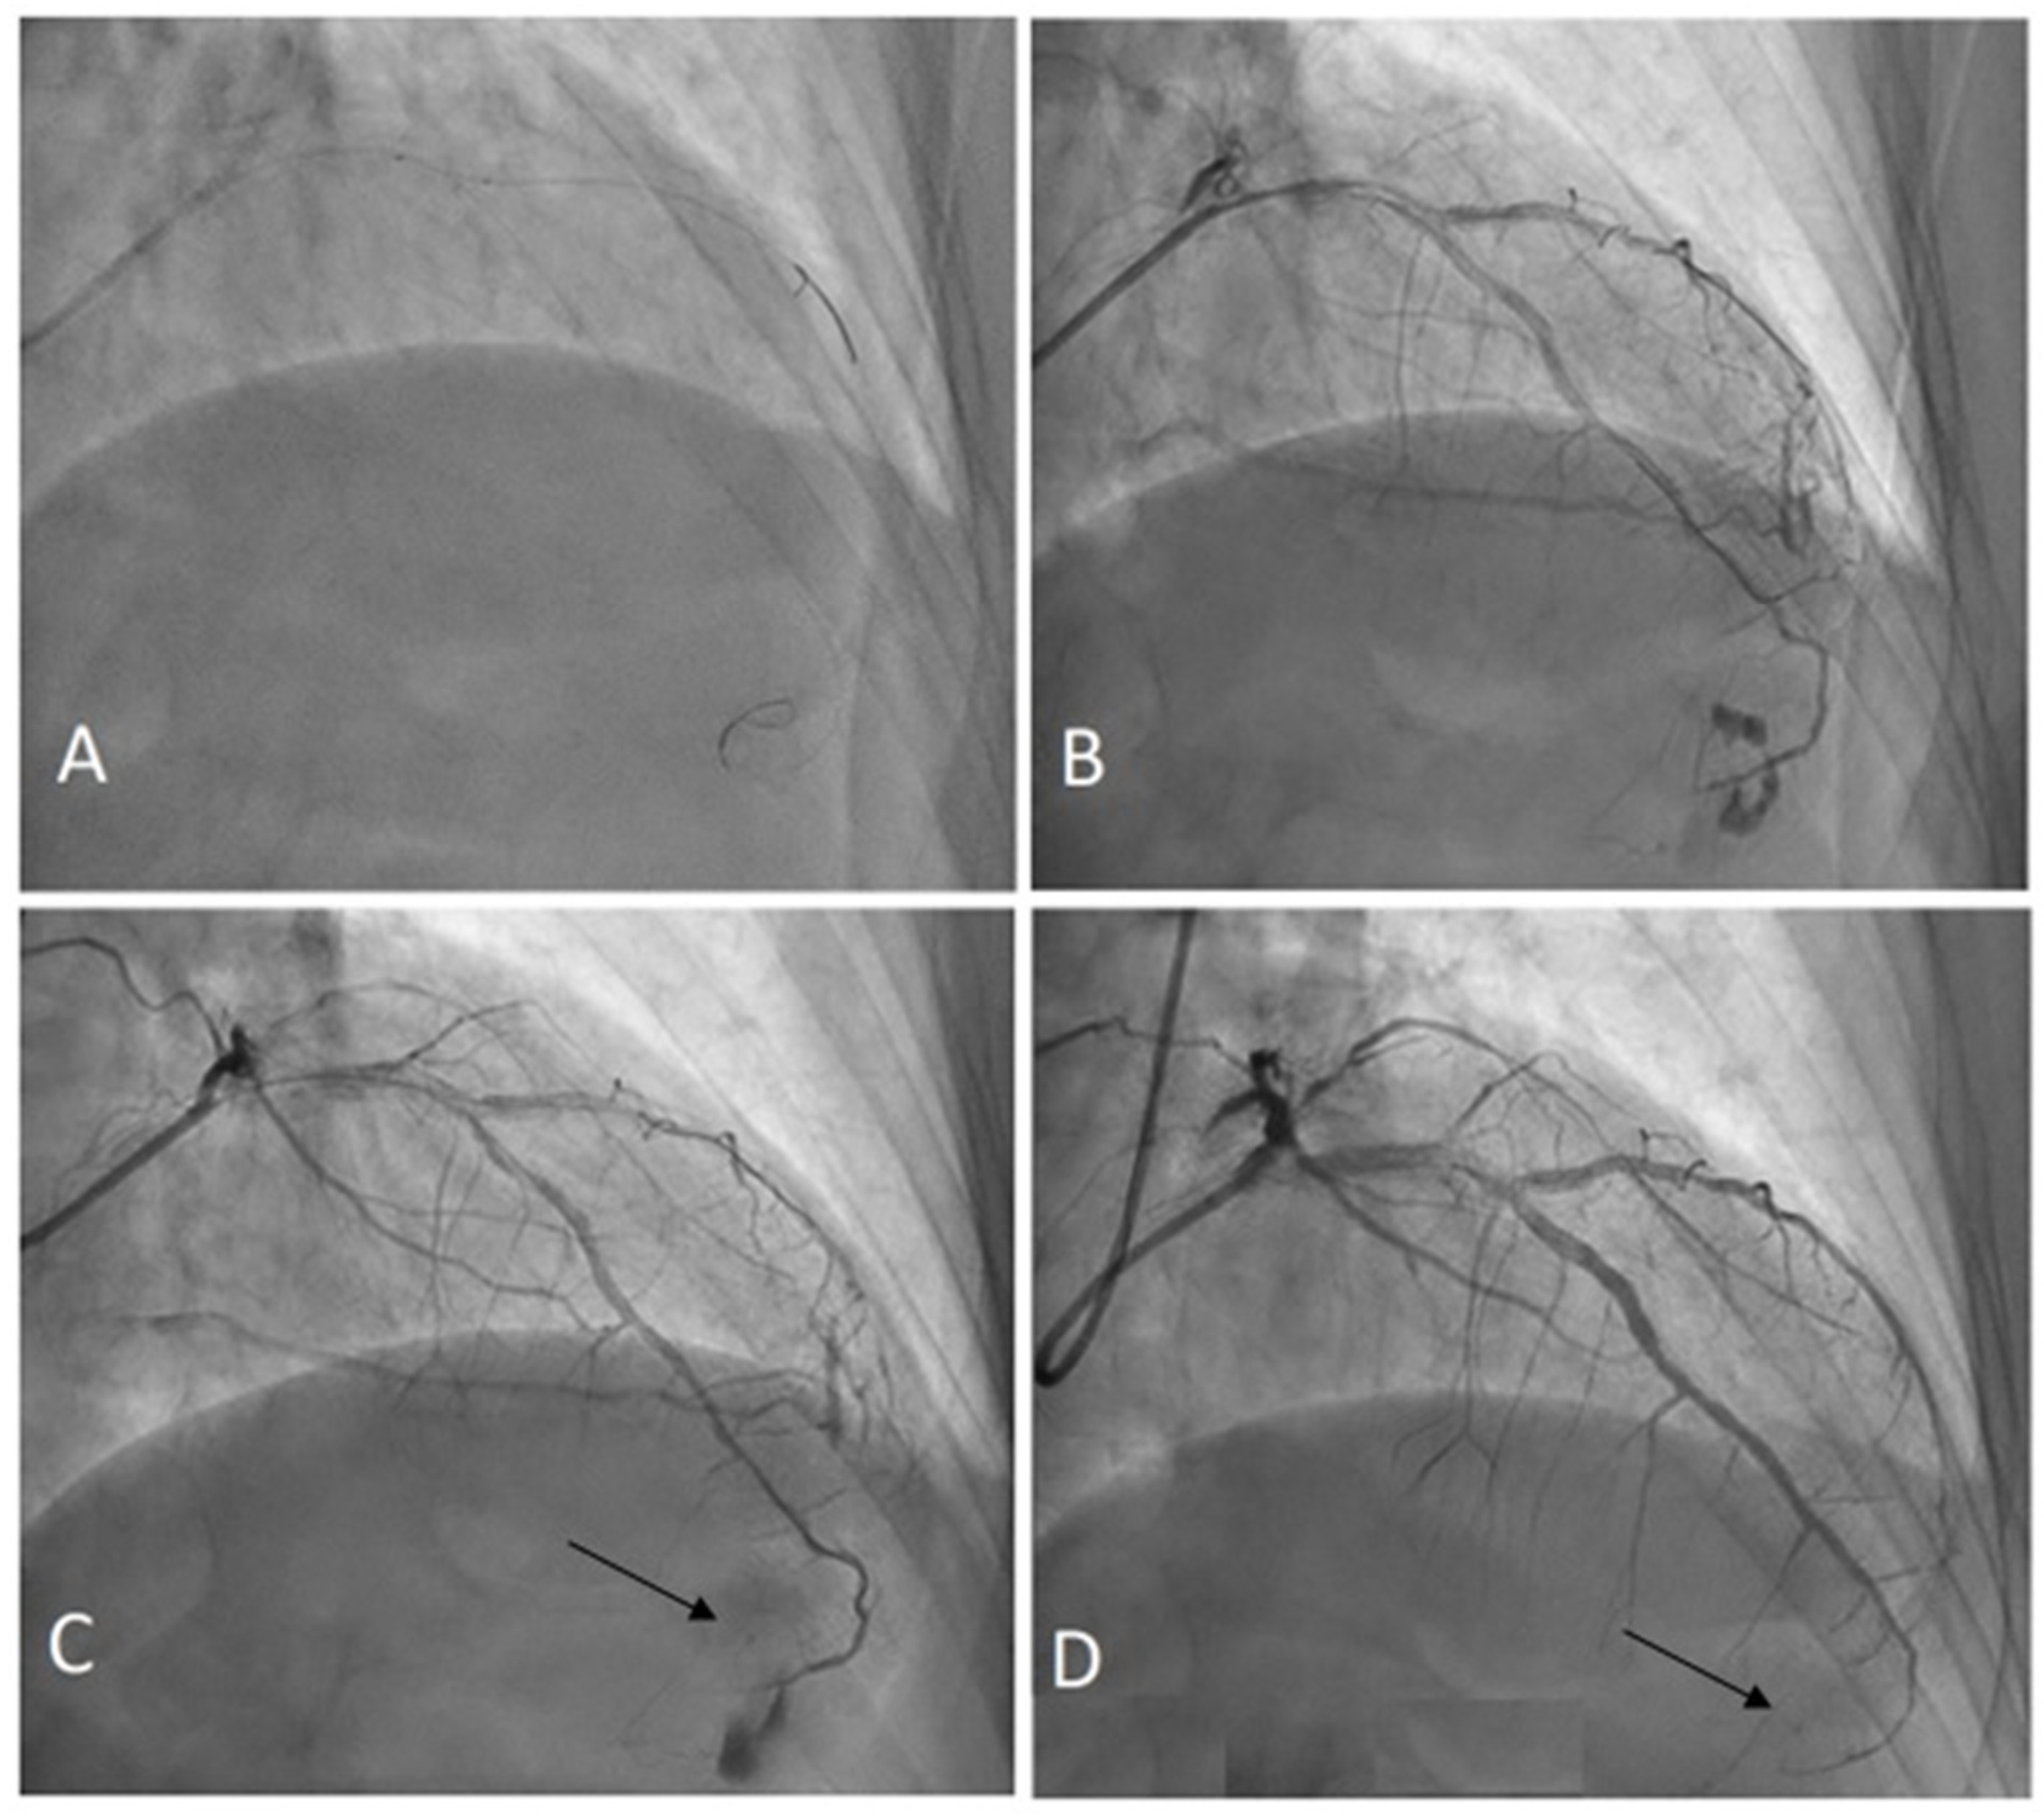

Embolization of Perforated Coronary Artery with a Fragment of Balloon Catheter (Cut Balloon Technique)—Multicenter Study

- Sobieszek, G.; Zięba, B. Balloon Fragment Technique Used to Close Distal Coronary Vessel Perforation. J. Invasive Cardiol. 2020, 32, E370–E372. [Google Scholar] [PubMed]

- Öcal, L.; Yılmaz, C.; Uysal, S.; Cerşit, S.; Zehir, R. Successful management of distal coronary artery perforation with the modified cut balloon technique during percutaneous coronary intervention. Anatol. J. Cardiol. 2022, 26, 66–68. [Google Scholar] [CrossRef] [PubMed]

- Alavi, S.H.; Hassanzadeh, M.; Dehghani, P.; Mehdipour Namdar, Z.; Aslani, A. A Novel Technique for Managing Guidewire-Induced Distal Coronary Perforation Using Coronary Balloon Pieces. JACC Case Rep. 2022, 4, 137–141. [Google Scholar] [CrossRef] [PubMed]

- Abdalwahab, A.; McQuillan, C.; Farag, M.; Egred, M. Novel economic treatment for coronary wire perforation: A case report. World J. Cardiol. 2021, 13, 177–182. [Google Scholar] [CrossRef] [PubMed]